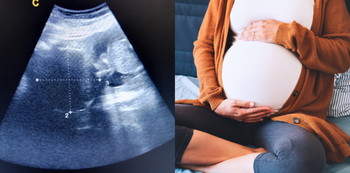

Wanita hamil umumnya hanya mengetahui mempunyai fibroid ketika menjalani ujian ultrabunyi dan tidak mengalami masalah ketika hamil. Fibroid biasanya akan mengalami pengecutan selepas kelahiran anak.

Oleh itu bagi wanita hamil yang mengalami fibroid, mereka haruslah melakukan pemeriksaan berkala untuk memastikan pembesaran janin berlaku dengan baik.